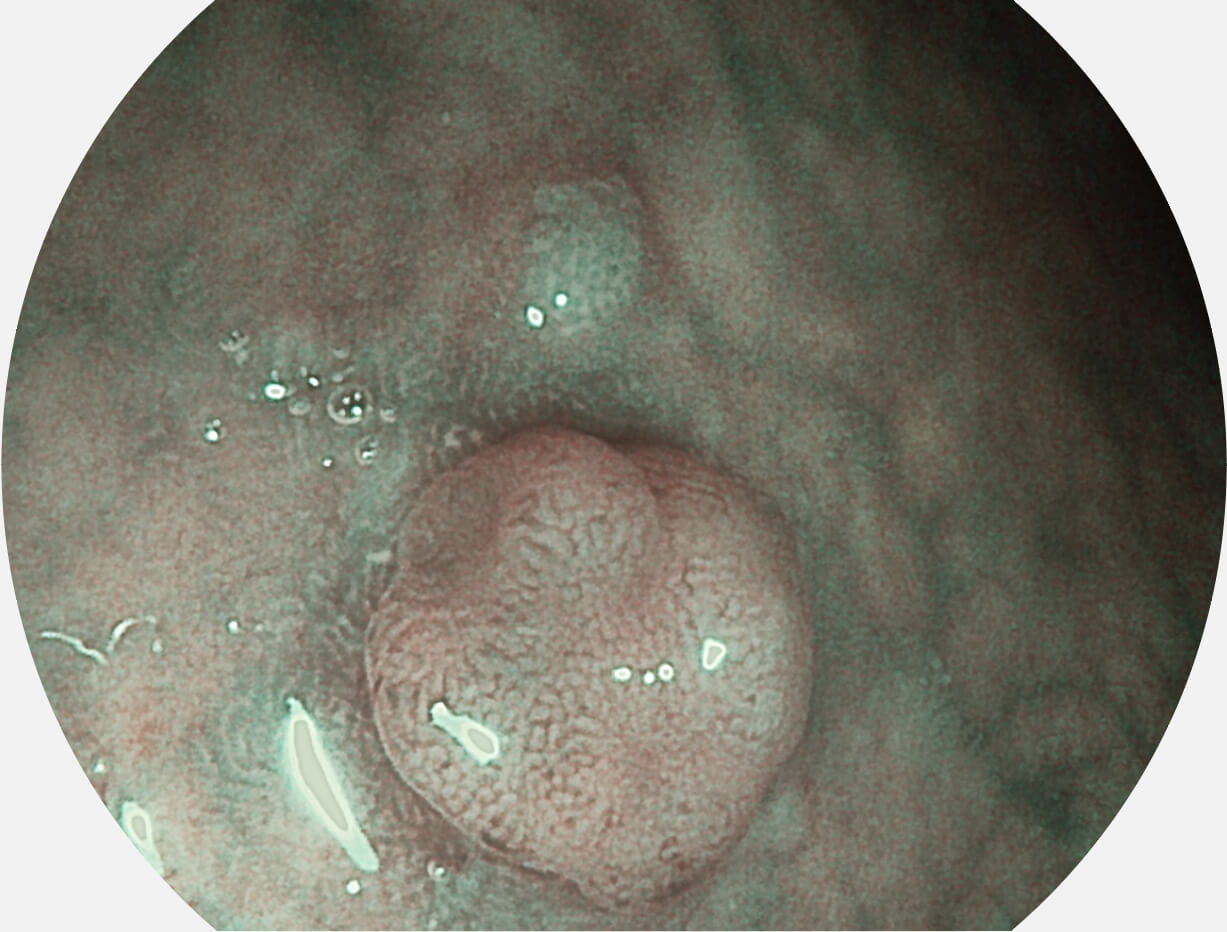

SFI图像

白光图像

图像具有高亮度、高黏膜血管颜色对比度的特点,且不改变粘液、食物残渣、粪便的基本颜色,可在中远景下进行观察,助力消化道早期疾病的诊断。

采用光路合束技术,光谱自由度高,实现了更丰富的照明模式,染色模式SFI及VIST,从远景到近景,助力消化道早期疾病诊断。